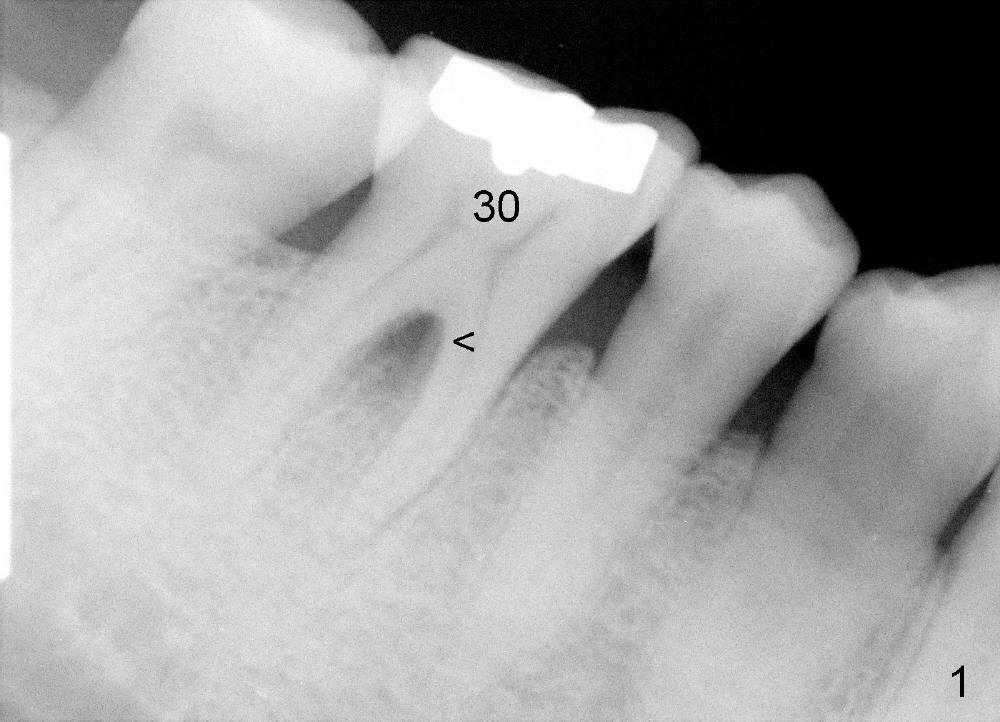

A 47-year-old man has had perio infection in the lower right 1st molar twice (Fig.1,2). Buccal and lingual furca pockets are ~ 9 mm. Following extraction and sectioning the septum, the osteotomy is initiated with a 2 mm pilot drill (Fig.3). Although the drill deviates into the mesial socket, the coronal end is controlled more or less in the middle of the edentulous area (compare white and red lines). Ideally the axis of the osteotomy (Fig.4 red line) should be parallel to that of the 2nd molar and perpendicular to the curve of Spree. The coronal end of the 3.5 mm reamer (Fig.5) and of the 7x17 mm tap (Fig.6 T) remains in the center of the edentulous space. The apical threads of the tap are engaged into the bone for stability (Fig.6 <). When 7x17 mm implant is placed with > 60 Ncm, the mesial socket is obliterated while the density of the distal one increases because of autogenous bone grafting (Fig.7*).

When a large implant is placed in a molar socket, one dimension of the remaining socket is small (buccolingual for lower, mesiodistal for upper). It is apparent that the mandibular buccal and lingual gingiva is relatively loose for the most time, the mesial and distal socket could be closed by suturing and perio dressing. The maxillary palatal gingiva is particularly thick and tough to be approximated. It appears necessary to develop a technique using an immediate provisional to close the socket or place an abutment. Cortex-like bone seems to have grown into the mesial thread spaces 3 years post cementation (Fig.13 <). The 7x17 mm implant was placed buccal (Fig.14 B). The slowly resorbed buccal plate seems to darken the buccal gingiva (Fig.15 B). The bone next to the implant is dense 6 years post cementation (Fig.16 *). The implant at 19 should be smaller and placed lingual.